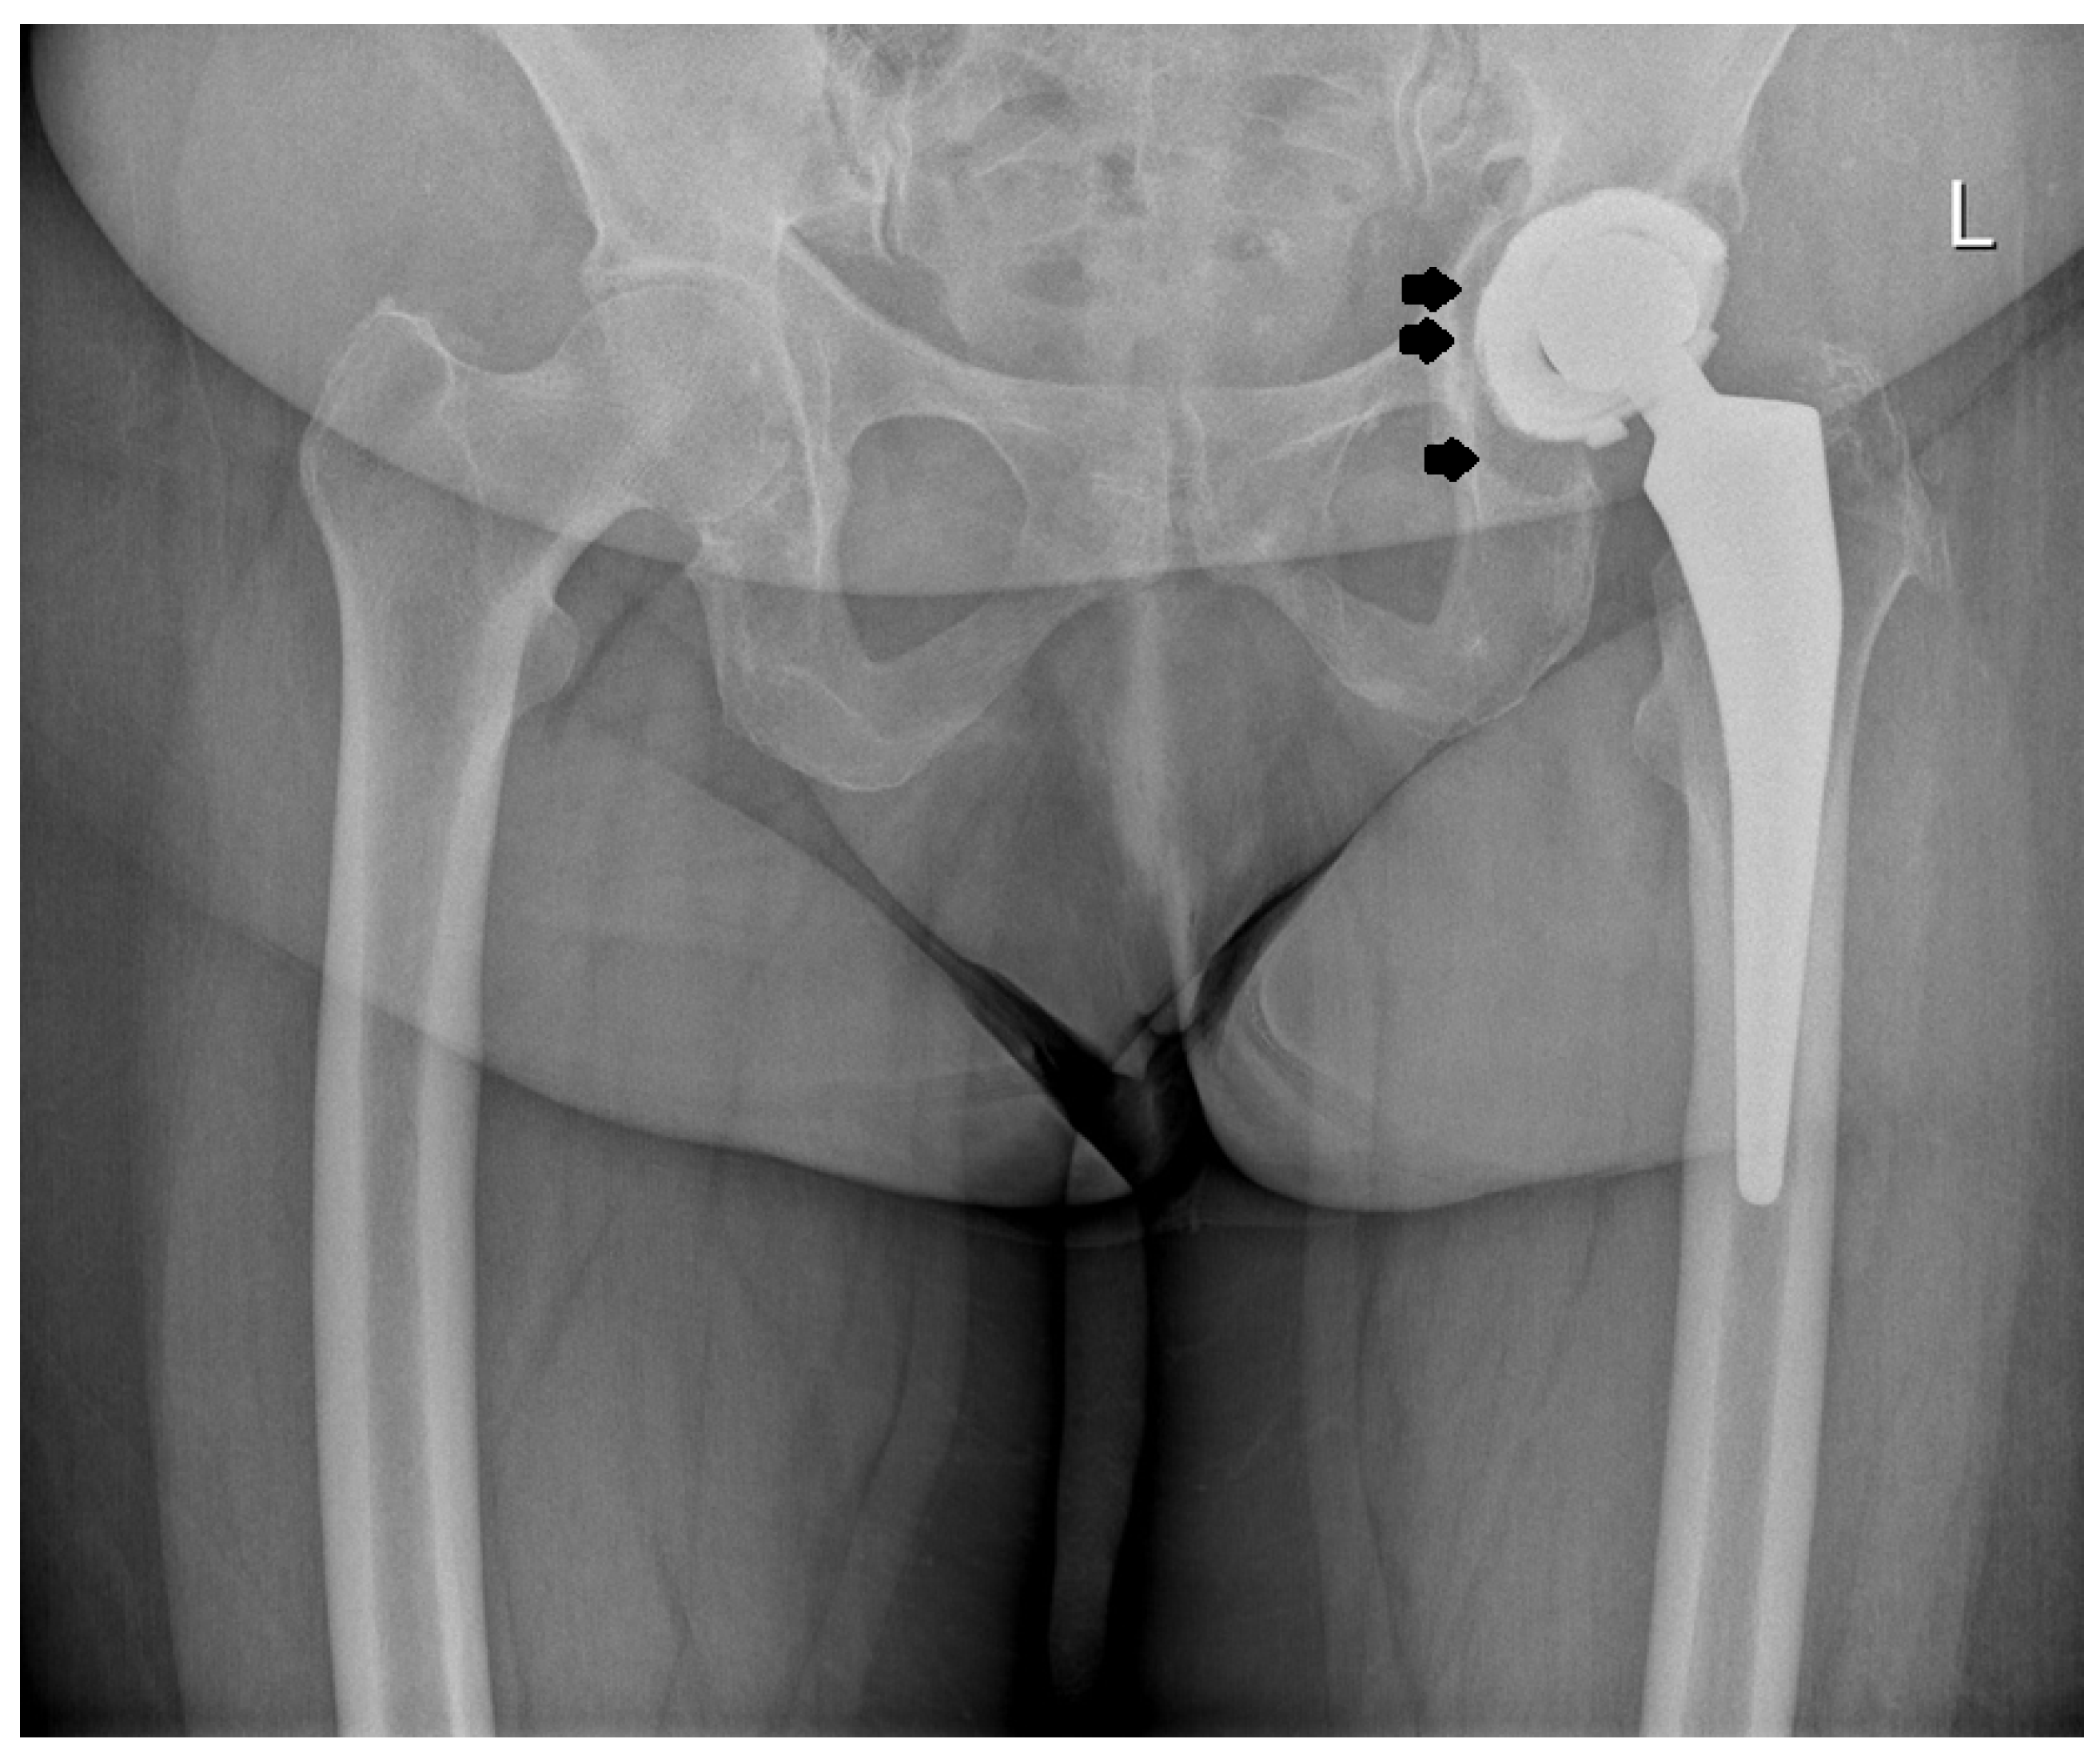

2.2. Design of the L-Cup Acetabular Component

2.4. Acetabular Implantation